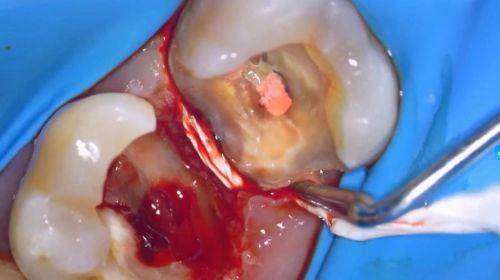

第一次治疗:医生会精良行局部麻醉,这样在治疗过程中你就不会感到疼痛。然后消除炎症和感染,并在根管内插入药物。这些药物就像是“小卫士”,能帮助控制炎症,为后续治疗打下基础。

第二次治疗:去除根管内的失活剂,然后反复冲洗根管。接着开始根管预备,让根管通畅,把里面的炎性物质引流出来。之后对根管进行换药和消毒处理,进一步消除炎症。

第三次治疗:使用牙科专用充填材料对根管进行充填。这一步就像是给牙齿的“内部通道”加上了一道“防护墙”,隔绝外界刺激,杜绝再次感染。